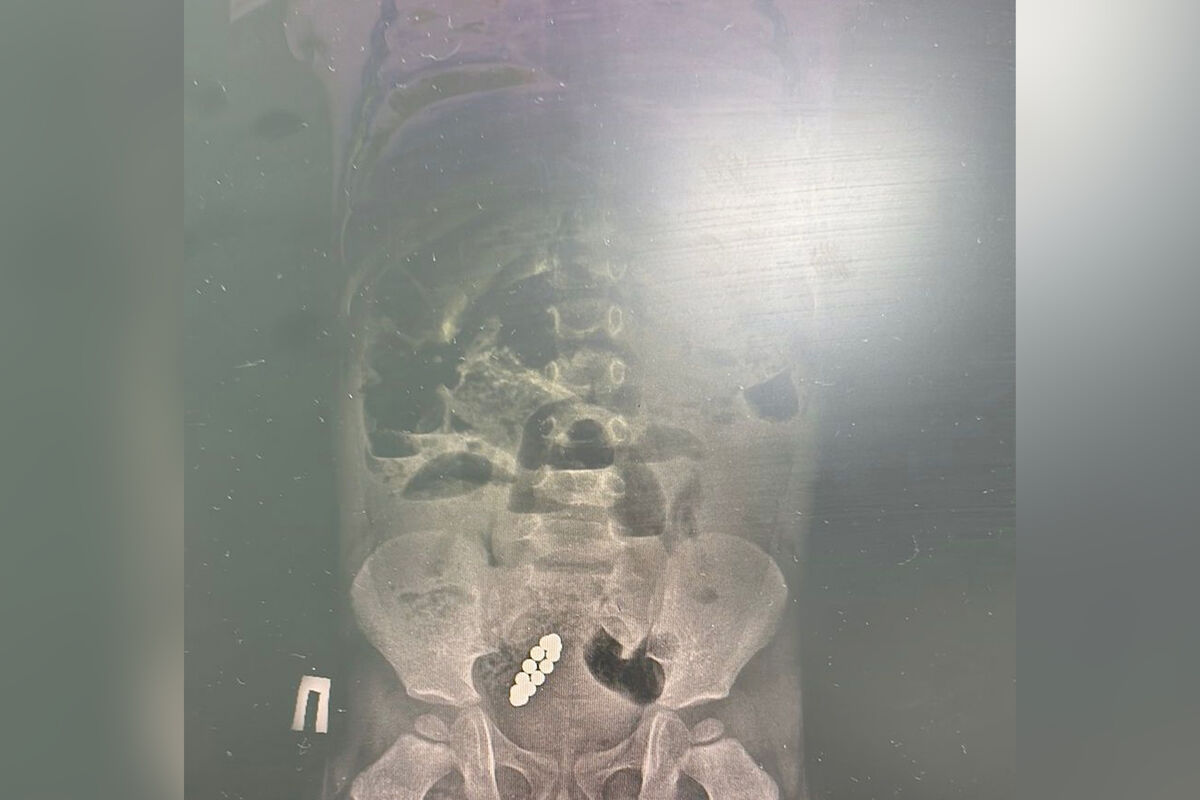

Тянули с больницей: ребенок жил с 13 магнитами в ЖКТ девять дней

В Казахстане спали ребенка с 13 магнитами в кишечнике, он жил с ними девять дней

Врачи Центра детской и неотложной помощи в Алматы (Казахстан) спасли семилетнего ребенка, который больше недели проходил с 13 магнитами в кишечнике. Об этом сообщили в пресс-службе медицинского учреждения.

По информации врачей, мальчик почувствовал недомогание 27 января. Родители отвезли сына в частную клинику, где на рентгене увидели магниты и рекомендовали обратиться в больницу. Но родители приняли решение «наблюдать за состоянием ребенка самостоятельно» и повторно показали сына врачам через девять дней, когда у него началась рвота до 15 раз в день. Мальчика экстренно госпитализировали в Центр неотложной помощи.

«Диагноз – острая низкая кишечная непроходимость и инородное тело в желудочно-кишечном тракте. Нам пришлось выполнить две сложные операции», — рассказал хирург медучреждения, добавив, что из кишечника мальчика удалили 13 магнитов.

Медики отметили, что маленького пациента выписали, ребенок чувствует себя хорошо.